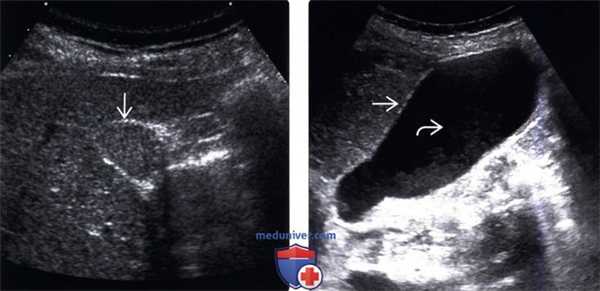

(Левый) На поперечном УЗ срезе определяется сладж, заполняющий желчный пузырь. Сладж имеет такую же эхогенность, как и печень, это состояние называют «гепатизацией».

(Правый) Положение пациента на левом боку. На продольном УЗ срезе визуализируется смещающийся книзу под действием гравитации сладж, напоминающий полип. Стенка желчного пузыря не изменена.